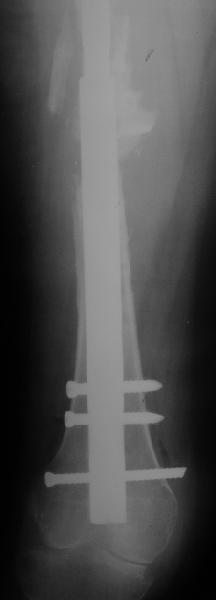

Female, rheumatoid, THA in 2003, car accident in 2006, failed plating. Nailing in Oct 2007. The nail is solid with hollow proximal part where the stem is docked. Last images are in 1 year after

nailing.